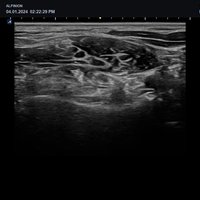

Mit dem X-CUBE 50 erweitert ALPINION seine X-CUBE Serie an hochmodernen Ultraschallgeräten. Das X-CUBE 50 bietet mithilfe der X + Architecture und einem besonders abgestimmten Sondenportfolio, zu dem auch Single Crystal Schallköpfe unserer High-End Systeme gehören, eine extrem wirtschaftliche Ultraschalllösung mit beeindruckender Bildqualität.

Dieses intelligente Ultraschallsystem, das auf automatisierten Tools und einem verbesserten Workflow basiert, ermöglicht den Verzicht häufiger Anpassungen durch den Arzt und erhöht so die Genauigkeit und Effizienz bei der Diagnostik. Mit seiner kompakten Bauweise ist das X-CUBE 50 auch in kleinen Behandlungszimmern einsetzbar.

X + Architecture

Die X + Architecture ist eine innovative Technologie, die von ALPINION entwickelt wurde, um die Leistung und Effizienz der Ultraschallsysteme zu verbessern. Durch die Integration fortschrittlicher Algorithmen und Hardwarekomponenten ermöglicht die X + Architecture eine schnellere Bildverarbeitung, höhere Bildqualität und eine präzisere Diagnose. Diese Technologie trägt dazu bei, die Genauigkeit und Zuverlässigkeit der Ultraschalluntersuchungen zu steigern und den Arbeitsablauf in medizinischen Einrichtungen zu optimieren.

X + Fit

Die ausgefeilte parallele Beamforming-Technologie X + Fit ermöglicht durch das Senden, Empfangen und Verarbeiten großer Datenmengen in hoher Geschwindigkeit eine Verbesserung von Kontrast und Gleichmäßigkeit für eine hervorragende Auflösung.

Durch den Einsatz der harmonischen Signalverarbeitungstechnik werden Signalverluste minimiert und die Bandbreite des vom Schallkopf übertragenen Signals verbessert. Dies führt zu einer Reduzierung von Artefakten und gleichzeitig werden Auflösung, Kontrast und SNR verbessert, so dass eine optimale Darstellung von Läsionen ermöglicht wird.

Full SRI TM – Speckle Reduction Imaging